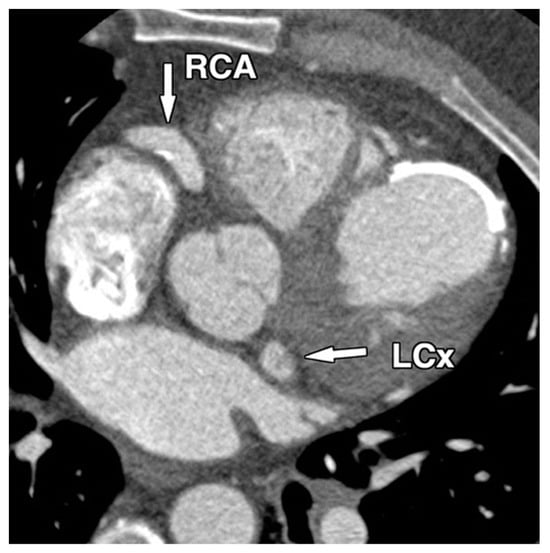

1.1. Diagnostic